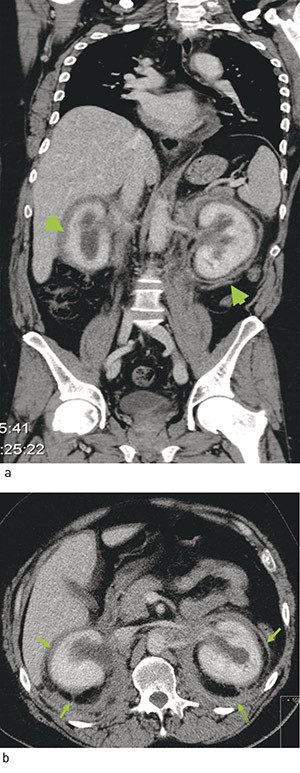

CT thorax og abdomen viste bløtdelsoppfylling langs aorta i flere nivåer, og i nedre del omkranset vevsfortykkelsen hele aorta. Fra nivå med nedre nyrepol og til bifurkaturen var det utbredelse som ved retroperitoneal fibrose med fortykket perirenale fascie. Innenfor perirenalt fettvev var også begge nyrekapsler fortykket med forandringer vel forenlig med «hairy kidneys» (fig 2). Begge nyrebekkener var dilatert, uten utvidelse av ureter.

Et karakteristisk funn ved Erdheim-Chesters sykdom er infiltrasjon av perirenalt vev, som på CT kan ses som «hairy kidneys». Dette kan påvises hos opptil 68  % av pasientene (5), og ble også funnet hos vår pasient.